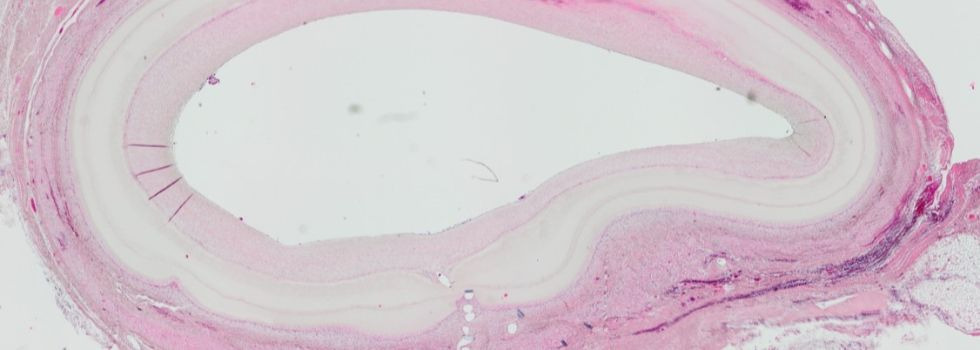

Cardiovascular Tissue Engineering

Artificial Bypass - Tissue Engineering in Cardiac Surgery

With a share of more than 50%, bypass surgery represents the largest share in the cardiac surgery portfolio. Every year alone in the US and Germany together… more.